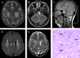

Neuroaxonal dystrophy

Infantile neuroaxonal dystrophy is a rare pervasive developmental disorder that primarily affects the nervous system. Individuals with infantile neuroaxonal dystrophy typically do not have any symptoms at birth, but between the ages of about 6 and 18 months they begin to experience delays in acquiring new motor and intellectual skills, such as crawling or beginning to speak. [Source: Wikipedia ]